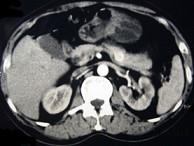

问题 男性,57岁,1年前无明显诱因反复出现嗜睡及发作性神志不清,进食糖水或甜品后症状即缓解,腹部CT检查如下图,最佳的诊断是()

选项 A.胰腺癌 B.胰岛细胞瘤 C.胰腺转移瘤 D.胃泌素瘤 E.舒血管活性肽瘤

答案 B